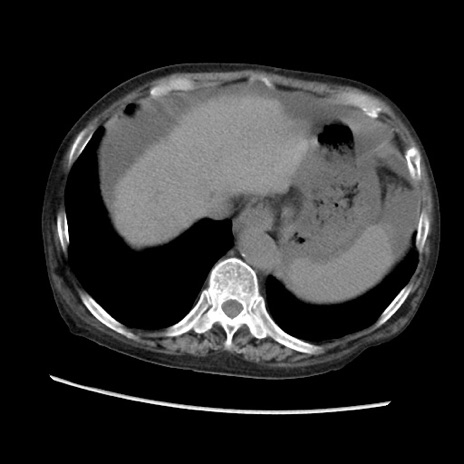

症例31(横断像)

【症例】80歳代 女性

【主訴】腹部膨満感

【現病歴】他院にて肝硬変にてフォロー中。1週間前から便秘、腹部膨満感、臍部腫瘤あり受診となる。

【既往歴】肝硬変

【身体所見】腹部膨隆あり、皮膚変化なし、疼痛なし。

【データ】WBC 4600、CRP 0.25